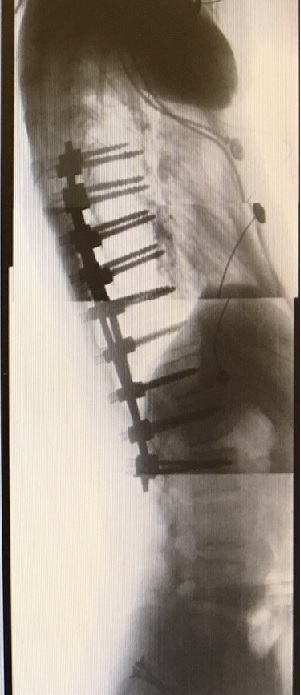

And here's a couple "after" shots:

Holy crap!  FYI those 18 screws are 45-50 millimeters long (50 millimeters is 2 inches), and 6 millimeters in diameter (about a quarter inch).  The two stainless steel rods are 12 inches in length.  Max now has two scars on his back over a foot long.  He was almost 6'2" when he went in, but we expect him to be 6'3" to 6'4" when he comes out.

He's in a lot of pain right now of course, but his prognosis is good, and we expect him to be coming home from the hospital on Friday.  He should be mostly back to normal in 6 weeks, and fully recovered in 3 months.  My wife, who is a physician, is staying with him at the hospital 24/7 and watching the other doctors and nurses like a hawk LOL!